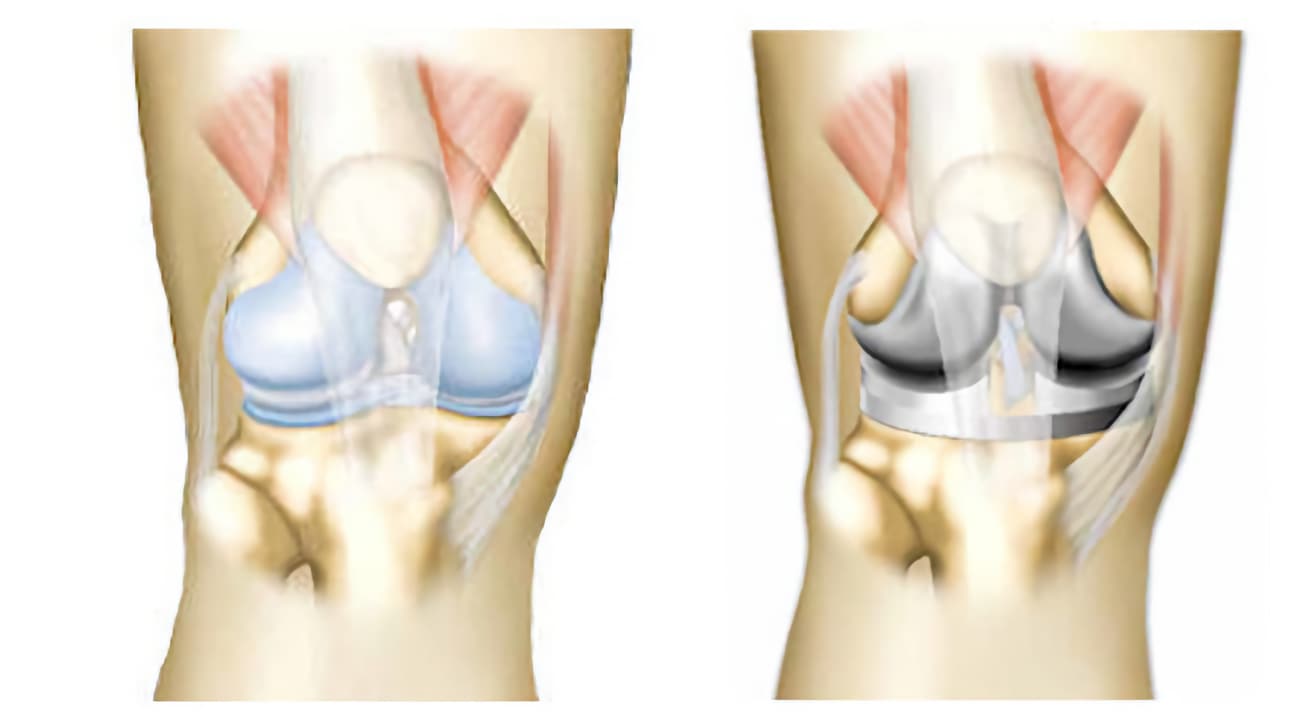

Άρθρωση είναι το σημείο όπου συνδέονται τα οστά μεταξύ τους, για να επιτρέπεται η κίνηση προς συγκεκριμένες κατευθύνσεις. Η άρθρωση του γόνατος επιτρέπει να λυγίζουμε και να τεντώνουμε το γόνατο όταν περπατάμε. Κατά τις κινήσεις αυτές, η κνήμη περιστρέφεται χωρίς να το συνειδητοποιούμε (αυτές οι κινήσεις ονομάζονται περιστροφικές).

Αυτή η άρθρωση στηρίζει το βάρος του σώματος και πρέπει να είναι σταθερή για να μην προκαλείται πτώση. Το γόνατο ενώνει το μηρό με την κνήμη.Το μηριαίο είναι το οστό του μηρού. Η κνήμη είναι το οστό που βρίσκεται κάτω από το γόνατο, στο μπροστινό μέρος του σκέλους, ενώ η περόνη βρίσκεται προς τα έξω και προς τα πίσω.

Καθώς το γόνατό σας έχει φθαρεί από αρθρίτιδα, η άρθρωσή σας έχει αντικατασταθεί από πρόθεση (πρόθεση γόνατος). Αποτελείται από ένα τμήμα τοποθετημένο στο μηριαίο και ένα δεύτερο στην κνήμη. Πρόκειται για ολική πρόθεση. Μερικές φορές υπάρχει και ένα τρίτο τεχνητό μέρος στο ύψος της επιγονατίδας (πρόθεση επιγονατίδας).

Τα τεχνητά μέρη της άρθρωσης είναι στερεωμένα στο οστό με ή χωρίς τη χρήση ειδικού τσιμέντου. Τα δύο μέρη της πρόθεσης ολισθαίνουν μεταξύ τους και αναπαράγουν τη φυσιολογική λειτουργία της άρθρωσης.